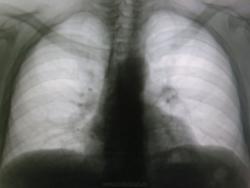

Шаровидное образование в левом лёгком

Мужчина молодого возраста проходил профосмотр и выявилось шаровидная тень. Жалоб пациент не предъявляет. От томограмм врачи отказались, сказав, что повезут его сразу на КТ. Как будут развиваться события дальше я не знаю. Хотелось бы посоветоваться с коллегами, что это. Предварительно я написал о кальцинате, добр. опухоль.

Слева в верхней доле, без томограмм тяжело что то говорить.

за ключицей?